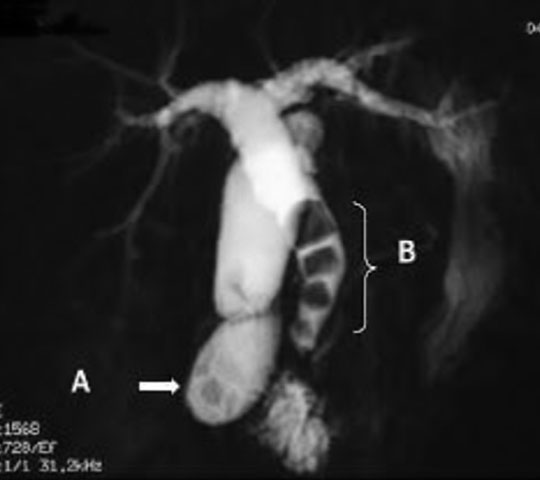

MRI 検査(Magnetic Resonance Imaging / 磁気共鳴映像法) とは、電磁石のトンネルの中に身体を入れ、磁気と電波 を使用して、身体の中の断面写真を得る検査です。現在、一般に使用されている画像診断法であるエックス線撮影やCT検査ではエックス線を使いますが、MRI検査では磁気と電波を使いますので、放射線被ばくの心配がありません。 また、身体の輪切り(横断面)の写真だけでなく、あらゆる角度の断面の写真を得ることができ、病気の部分の診断にたいへん役に立つ精密検査です。

MRCP(A:胆嚢結石 B:総胆管結石)